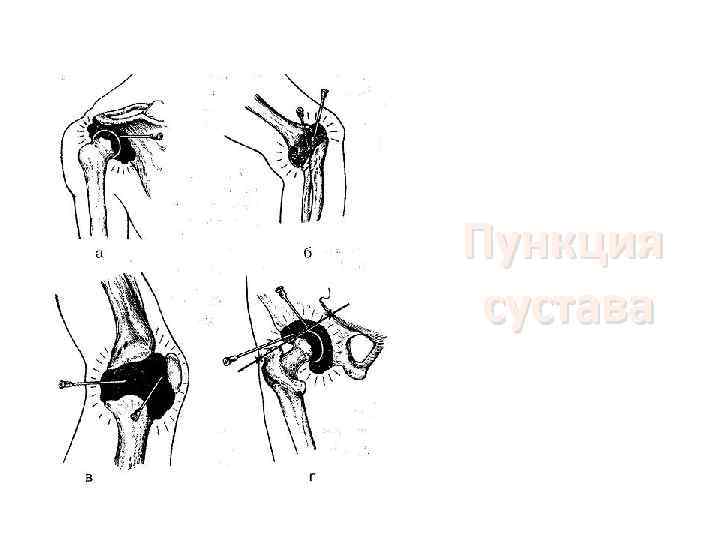

Пункция сустава

Пункция сустава